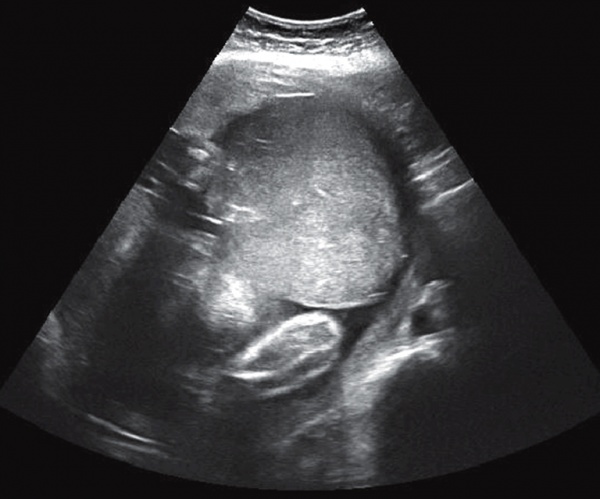

Между плацентой и миометрием определяется зона отрицательного эха. Можно примерно рассчитать площадь отделенной плаценты. Сердцебиение плода сохраняется до самой смерти, но двигательная активность снижается. Воротник закрыт, нормальной длины.

Ультразвуковая отслойка плаценты после огромной ретроплацентарной гематомы по данным УЗИ.